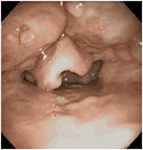

Surgical procedures to increase the volume of the retrolingual airway include lingual tonsillectomy, glossectomy, and advancement and suspension procedures. Figure 3 demonstrates lingual tonsil hypertrophy in a child who presented with obstructive sleep apnea after adenotonsillectomy. Lingual tonsillectomy may be performed with sharp dissection, monopolar dithermy (66), laser (67), or coblation (12, 54). The anterior midline of the tongue is controlled with a heavy silk suture, while an appropriately sized laryngoscope is used to expose the tongue base during lingual tonsillectomy (12). Lin performed coblation lingual tonsillectomies on 26 patients (aged 3–20 years) with polysomnography-proven persistent obstructive sleep apnea after adenotonsillectomy, as well as a diagnosis of lingual tonsillar hypertrophy made by flexible fiberoptic sleep endoscopy. Comparison of pre-operative and post-operative PSG demonstrated statistically significant reductions in the respiratory distress index (12). Complications related to lingual tonsillectomy include edema (67) and adhesions between the epiglottis and tongue base (68).